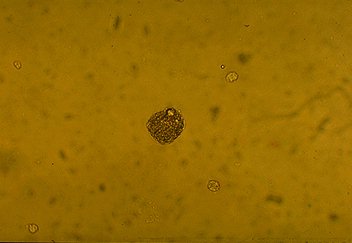

Oval fat body